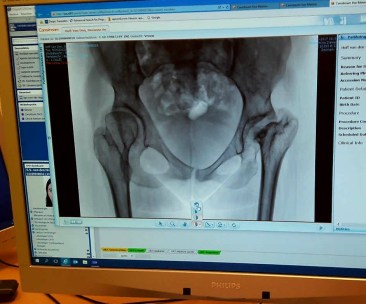

Anderhalf jaar geleden begon ik last te krijgen van mijn heup. Op sommige dagen voelt

het alsof mijn heup van mijn lichaam af wilt vallen, dat voelt echt heel akelig. Voor mij was dit ook echt een teken dat ik het rustiger aan moest gaan doen. Het is namelijk echt mijn eigen schuld dat mijn heup nu zoveel pijn doet. Naast de shopsessies waarbij ik niet in een rolstoel ga zitten en de stapavonden werkte ik ook 2 jaar lang bij de COOP. Ik werkte hier als caissière en na een half jaar daar te hebben gewerkt kreeg ik de functie leidinggevende. Dit betekende soms 6